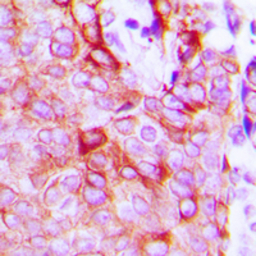

IHC-P analysis of formalin fixed human breast cancer tissue section using GTX55247 Latrophilin 2 antibody.

Antigen retrieval : Heat mediated antigen retrieval with sodium citrate buffer (pH 6.0)